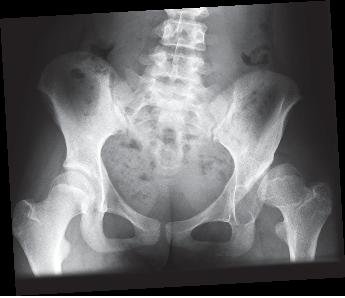

La o vârstă mai mare de 6 luni, din cauza nucleului de osificare a capului femural, mai ales dacă diametrul acestuia este peste 1 cm, diagnosticul devine dificil ecografic şi necesită examen radiografic.